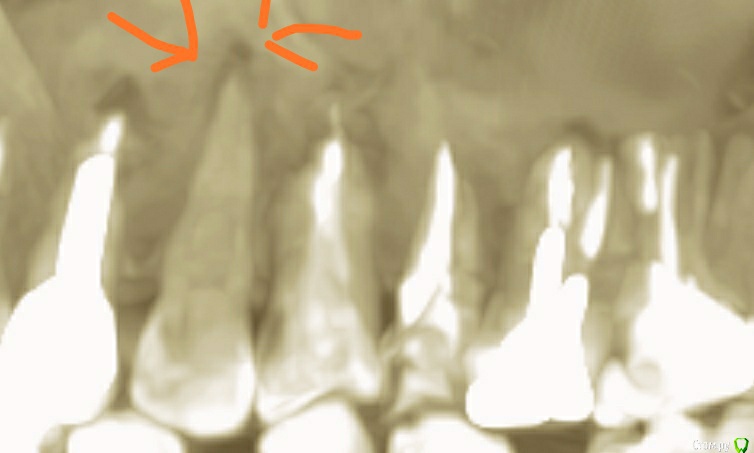

klemento Опубликовано 21 октября, 2019 Поделиться Опубликовано 21 октября, 2019 (изменено) Здравствуйте. Извиняюсь за беспокойство и открытие новой темы. Прилагаю КТ, лучше сделать нет возможности. Это лучшее, что можно было сделать в городе. Подскажите пожалуйста, что делать с зубами слева вверху. На данный момент беспокоит в области 5 и 6( и между ними) и в районе десны 4, а так же заложенность носа слева.Со вторым всё понятно - снимать и пломбировать нормально канал.Как я вижу на 3 тоже есть воспаление. С чего оно вдруг появилось не понимаю, зуб не беспокоит.На 4 нужно канал переделывать? Там вывод материала и как я вижу воспаление. В 5 положили кальций, но уже месяц пятно на снимке как было так и осталось и дискомфорт не прошел. Может там канал какой пропустили?С 6 снял коронку, т.к. воспалялась десна и боль была при накусывании. Его под удаление?7 вообще полный ппц, не знаю как так могли сделать, пропустить каналы и тд. Делал давно его. На данный момент не беспокоит, но как я вижу через панорамный - там большое воспаление. Его удалять или возможно спасти? 8 нормальный?Что тут вообще делать целесообразнее - пытаться спасти или выдирать и протезировать? Под микроскопом нет возможности лечить эти зубы. В городе ни в 1 клинике такой услуги нет, а в столице в 3-4 раза дороже чем обычное лечение и боюсь, что проще запротезировать. И не отдают ли эти зубы в пазуху, где видно пятно.Кт: https://dropmefiles.com/i82ov Изменено 21 октября, 2019 пользователем klemento Ссылка на комментарий

krokomot Опубликовано 21 октября, 2019 Поделиться Опубликовано 21 октября, 2019 Я же просил сделать вас снимок на визиографе, эта томограмма читабельна, лечите каналы 7ого, 4,6 каналы лечить не нужно,4,6,7 затем протезировать, 5й похоже на выход, очень похоже на перфорацию или трещину, в пазухе явления из-за воспаления вокруг корней 7ого. скаться в Минск из Гомеля не такая уж и непосильная проблема.... 2 Ссылка на комментарий

krokomot Опубликовано 21 октября, 2019 Поделиться Опубликовано 21 октября, 2019 проверте, возьмите маленький кусочек льда и приложите к 3 му если чувствуете холод то зуб живой, если нет то мертвый и требуется лечение, но у вас еще и второй с апикальным воспалением. Состояние периапикальных тканей на 4-м и 6м приемлимые такое явление с расширением бывает при контакте тканей периодонта с пломбировочным материалом корневого канала и в случае если каналы пломбированы качественно!!!, то можно такое оставлять, это вариант нормы, но зуб должен иметь герметичную пломбу и коронку. Я немогу ответить вам качественно ли проведено лечение ваших каналов, могу лишь сказать что такие периапикльные изменения как расширение периодонтальной щели до 0.44мм может быть вариантом нормы. Ссылка на комментарий